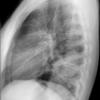

Case 2  Lingular pneum Lat

Date: 04/17/2005

Views: 6960